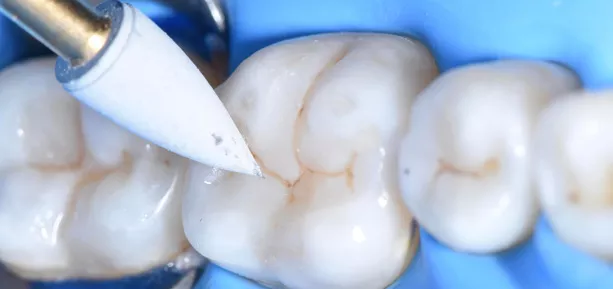

Fig. 9 Finishing of the restoration.

OptiDisc (Kerr) was used to carefully remove excess material from the buccal and lingual areas adjacent to the Class II restoration, ensuring a smooth and precise finish.